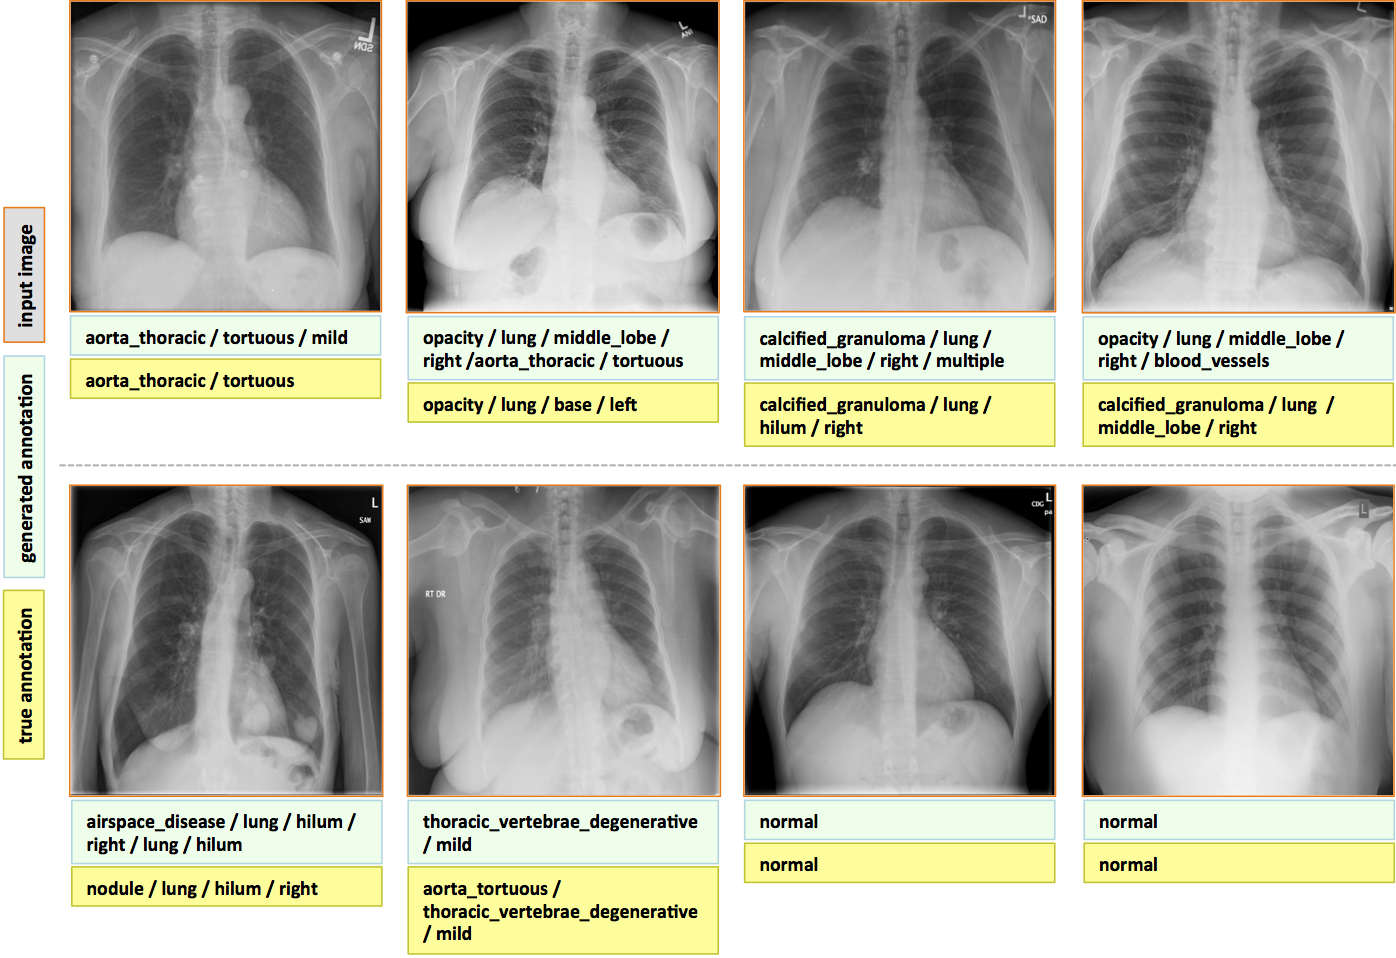

These generated captions are compared to the actual captions from the dataset and evaluated using BLEU scores as the evaluation metrics. A score closer to 1 indicates that the predicted and actual captions are very similar. As the scores are calculated for the whole test data, we get a mean value which includes good and not so good captions. Some of the examples can be seen below: